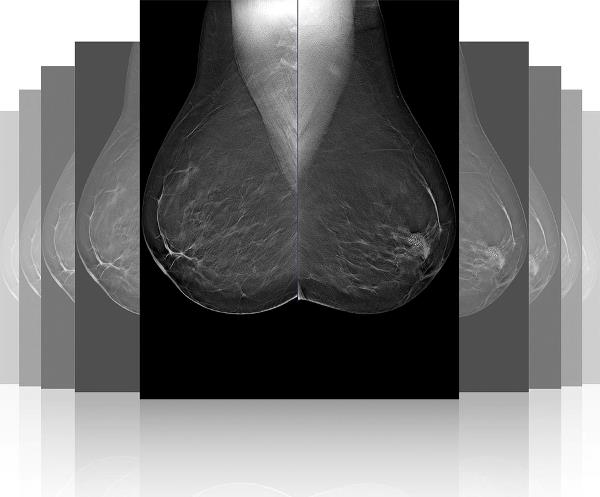

Томосинтез молочных желез: что это и как проводится исследование